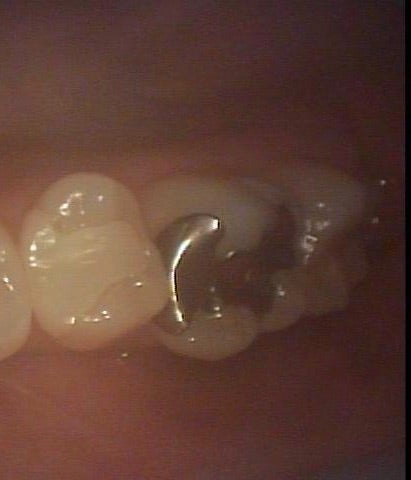

▶︎一見すると虫歯は無い様にも見えますが、、、

<銀歯を外した状態>

▶︎銀歯の縁や内部に黒い虫歯が発生しています。